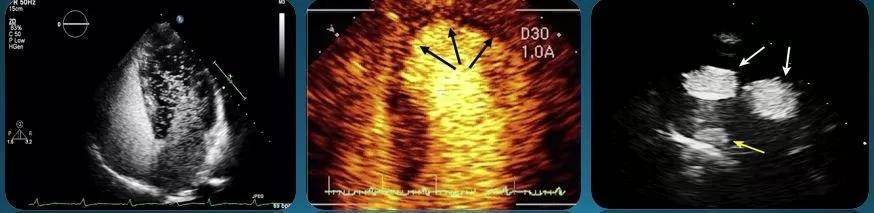

左图为右血管造影术显示的右向左分流。

中间图为心肌发育;

一般来说,右心对比超声心动图使用气泡。抽1毫升气体,用振荡盐水进行发泡实验,判断是否有左右分流。